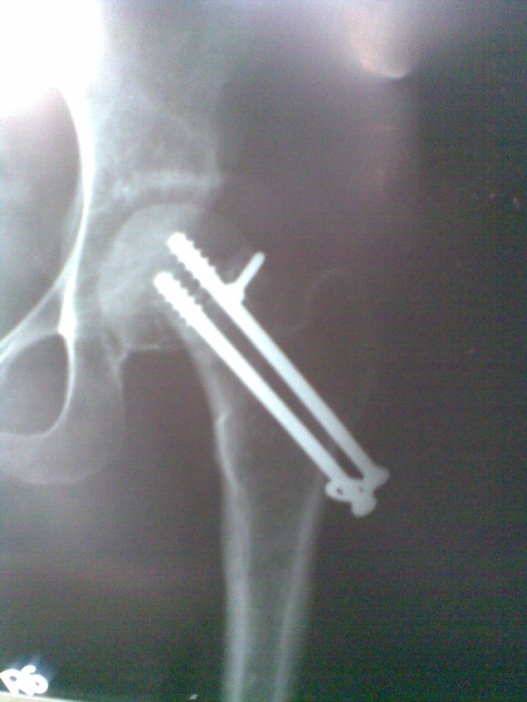

Spinal block was used in the procedure. Prone position on fracture table with radiolucent top was used. Fracture site was exposed through posterior approach and sclerosed margins of the fragments were freshened. Fracture was reduced with appropriate neck shaft angle and fixed with Moors pin/ knowels pin or 4 mm /7mm partially threaded cancellous screws. Any rotation or tilt was corrected. The fixation was augmented with quadratus femoris muscle pedicle bone graft harvested from intertochateric crest area with a bone pedicle of length 2 cm, width 1 cm and depth 1 cm. The graft was secured to the proximal femoral head fragment with 3.5mm cortical screw or 4mm cannulated cancellous screw. Soft tissue closure was done over drain.

First dressing change was done on third postoperative day and drain was removed at the same time. Sutures were removed on 14th day. Usually on 5th postoperative day quadriceps exercises was started. Non weight bearing was ensured for 4 months or till radiological union.

Patients were followed up at 2 weeks, 4 weeks, 6 weeks, 8weeksk, regularly at 6 week interval for next 6 month and then at three month interval up to two year. Radiographic analysis was performed at each follow up with special attention to extent of callus formation, alignment of fragments and hard ware integrity.